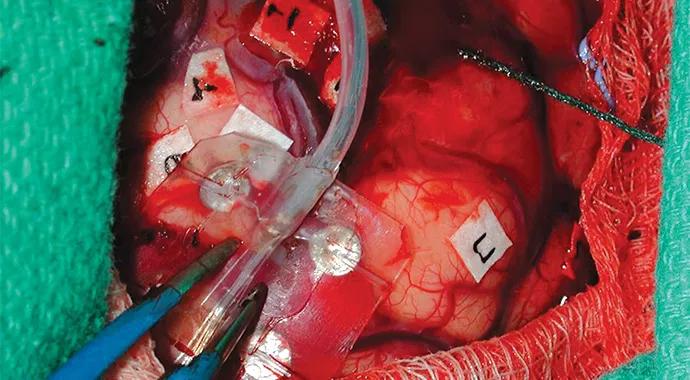

In some instances, invasive recordings can be accomplished in the operating room (intraoperative cortical stimulation and electrocorticography) under the safety of light anesthesia without the requirement of active patient cooperation (Figure 1).

Figure 1. Intraoperative photograph of exposed brain showing placement of a grid (held by forceps) on the surface of the brain for electrocorticography. The number tags lie over the brain regions that control eloquent function, already mapped by cortical stimulation. The resection strategy can be developed in the operating room safely and cost-effectively.